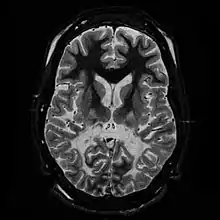

T2 weighted axial scan of a human brain at the level of the caudate heads demonstrates marked loss of posterior white matter, with reduced volume and increased signal intensity. The anterior white matter is spared. Features are consistent with X-linked adrenoleukodystrophy.

The degeneration of white matter, which reflects the degeneration of myelin, can be seen in a basic MRI and used to diagnose leukodystrophies of all types. T-1 and T-2 weighted fluid-attenuated inversion recovery (FLAIR) images are the most often used approach.[24] Electrophysiological and other kinds of laboratory testing can also be done. In particular, nerve conduction velocity is looked at to distinguish between leukodystrophy and other demyelinating diseases, as well as to distinguish between individual leukodystrophies. For example, individuals with X-ALD have normal conduction velocities, while those with Krabbe disease or metachromatic leukodystrophy have abnormalities in their conduction velocities.[24] Multigene sequencing panels for undifferentiated leukodystrophy are offered for rapid molecular diagnosis after genetic counselling.